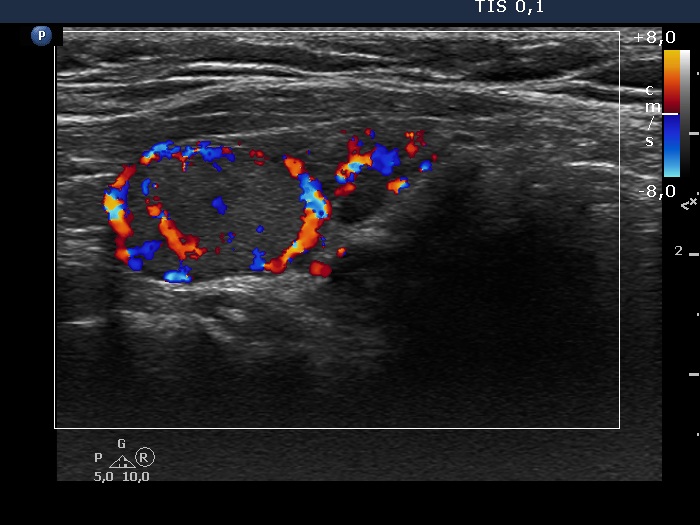

Consecutive patients with the final diagnosis of Hashimoto's thyroiditis - case 7 (851) (ultrasonographic picture 6)

Left lobe, longitudinal scan, color Doppler mode. The lesion has perinodular and intranodular blood flow.